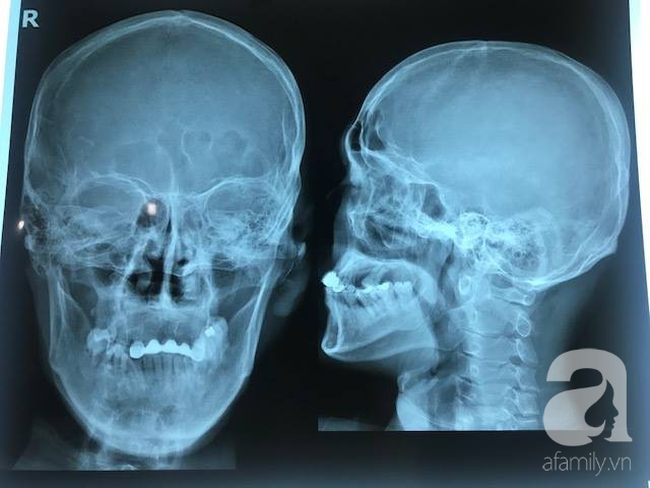

Sau các xét nghiệm cụ thể, bệnh nhân được xác định mang đa chấn thương rất nặng ở nhiều vị trí từ đầu đến chân trên cơ thể. Cụ thể là:

Phần đầu: gãy xương gò má - cung tiếp.